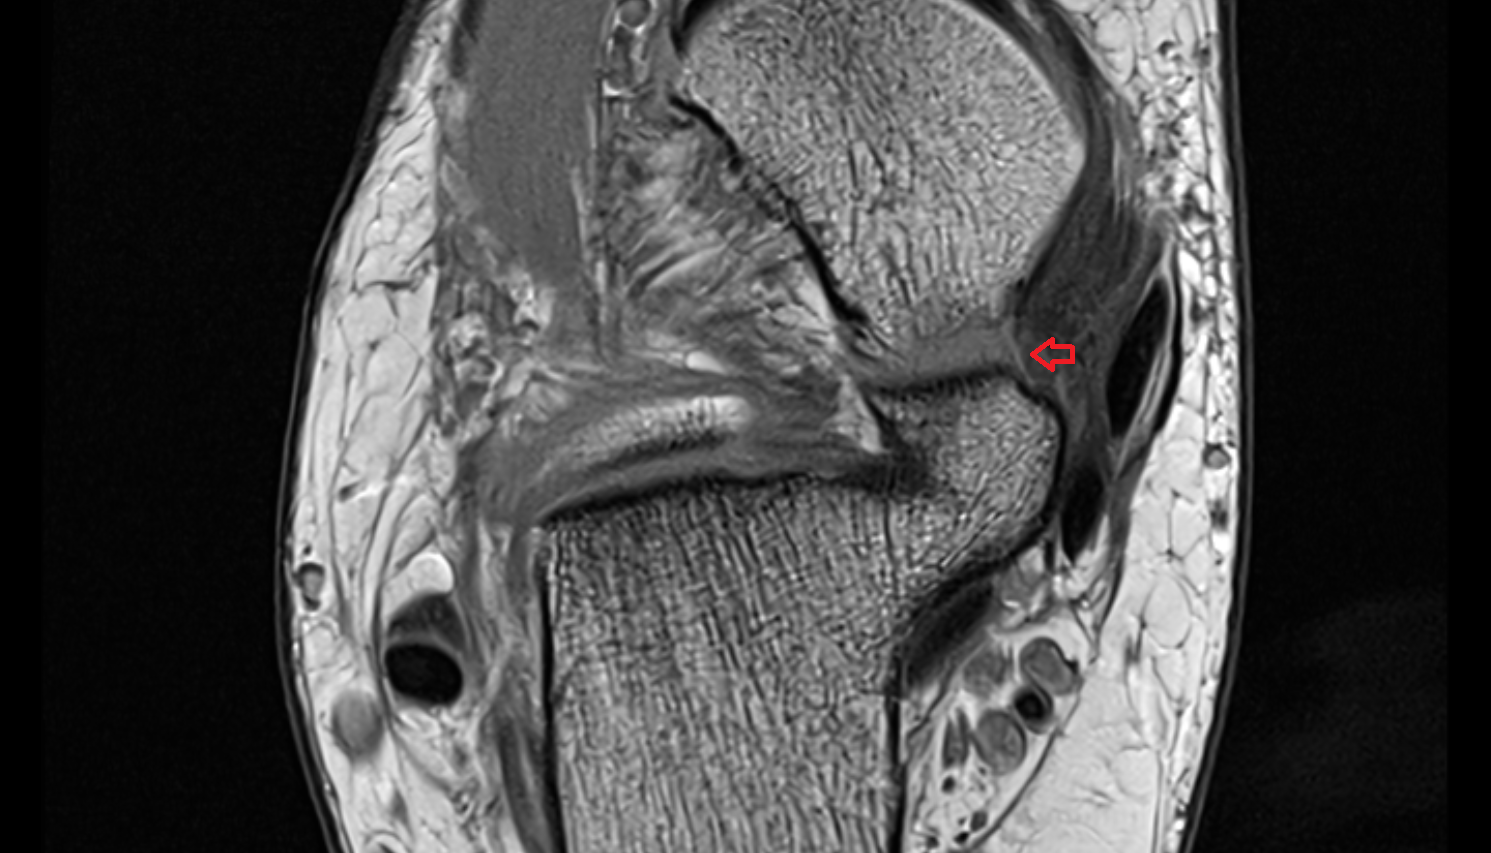

- Temporomandibular joint

- Articular disc of temporomandibular joint

- Articular eminence

- Mandibular condyle

- Mandibular fossa

- Superior head of lateral pterygoid muscle

- Inferior head of lateral pterygoid muscle